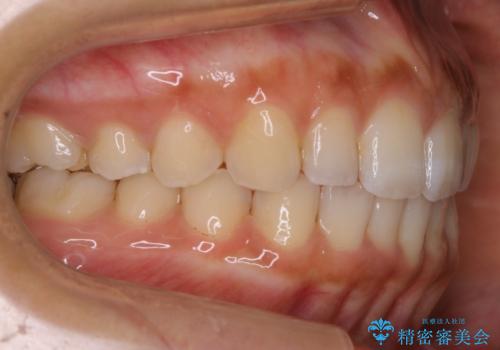

- 前歯のガタつきと噛み合わせの改善を希望してご来院されました。

目立たない装置での矯正治療をとのことでインビザラインを用いた非抜歯矯正を行うこととなりました。